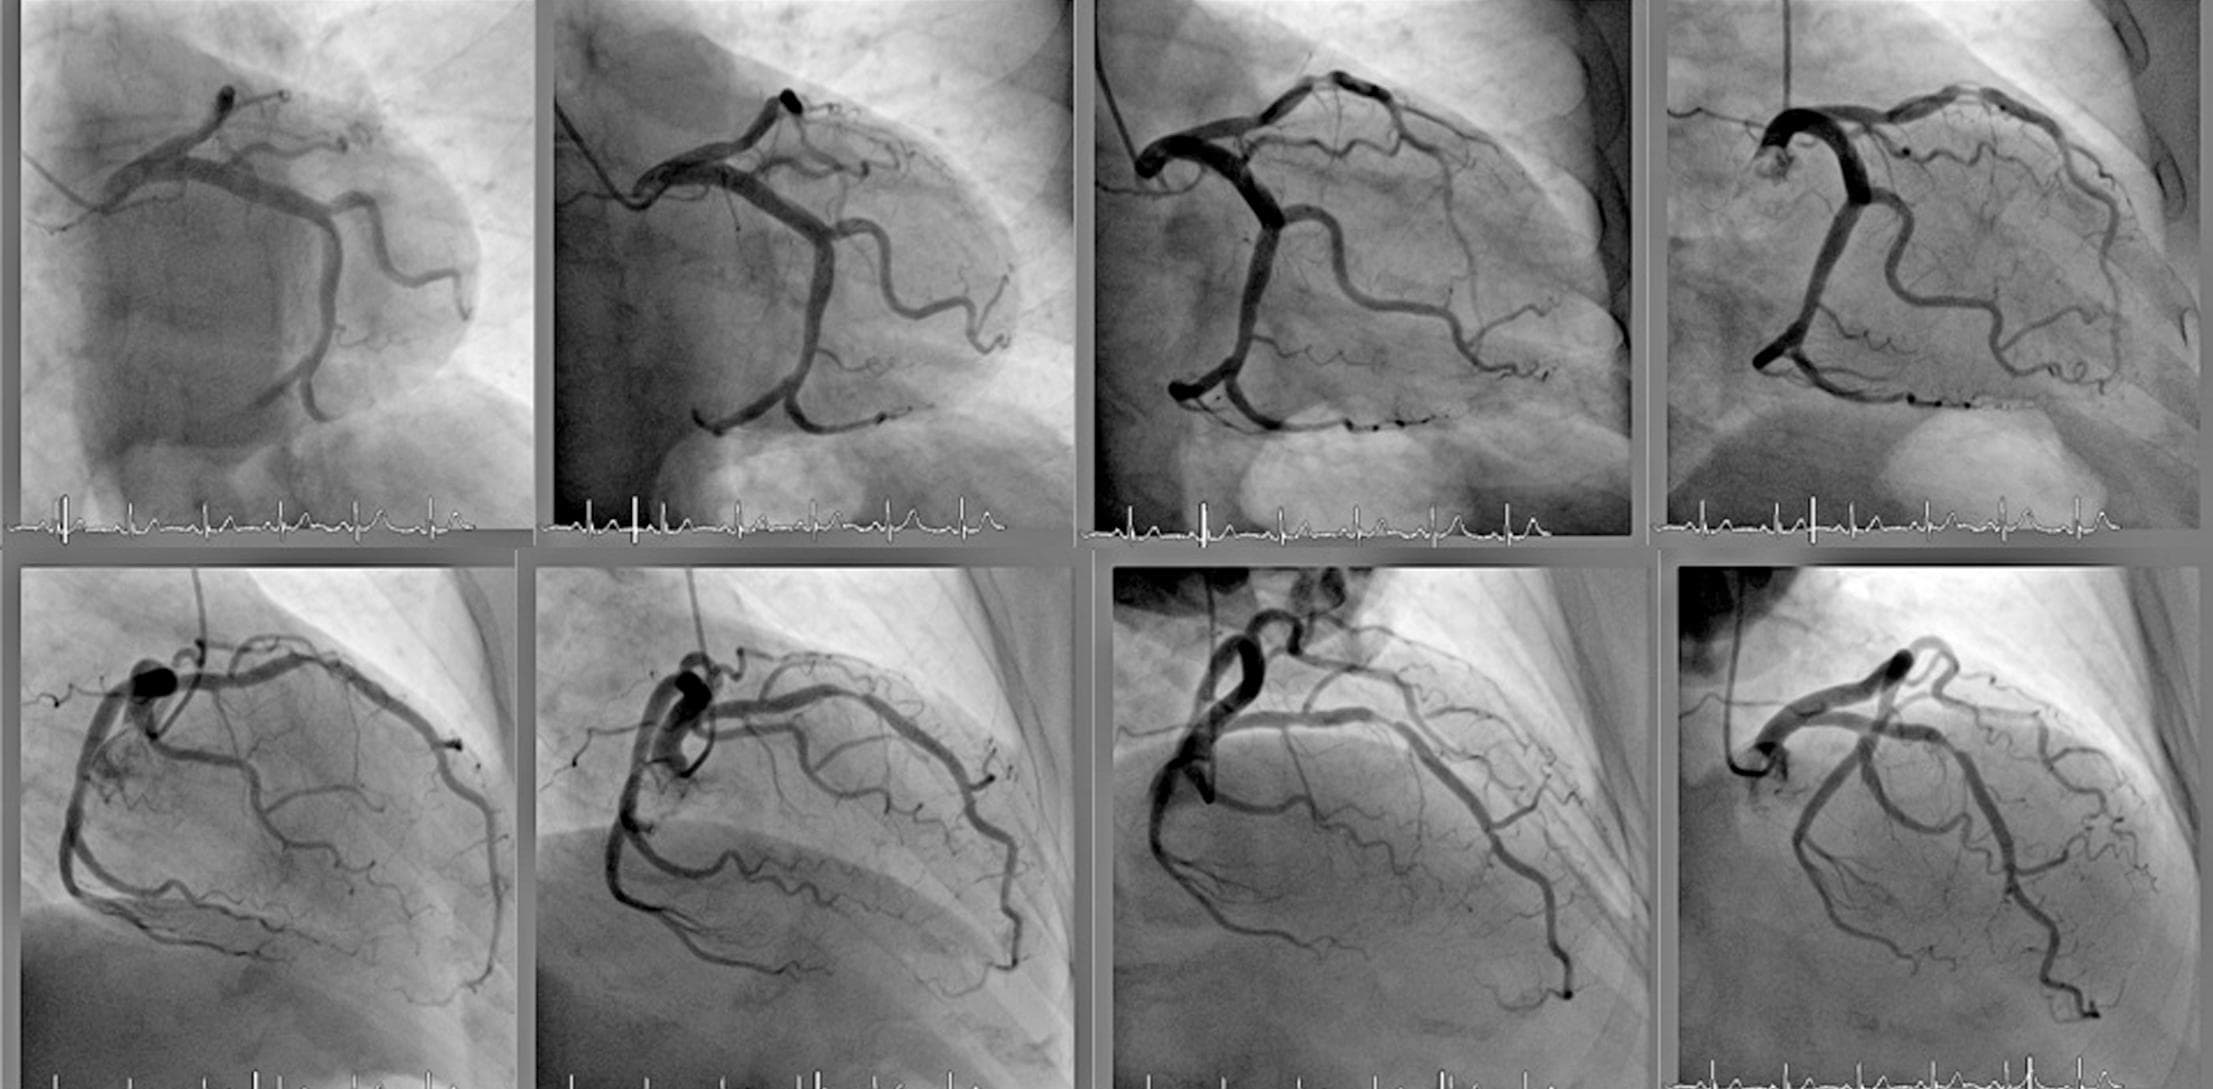

Beyin Anjiyografi

Beyin anjiyosu diğer adıyla serebral anjiyografi, beyindeki kan damarlarını görüntülemek için x-ışınları ve iyot içeren kontrast madde kullanılan minimal inv..